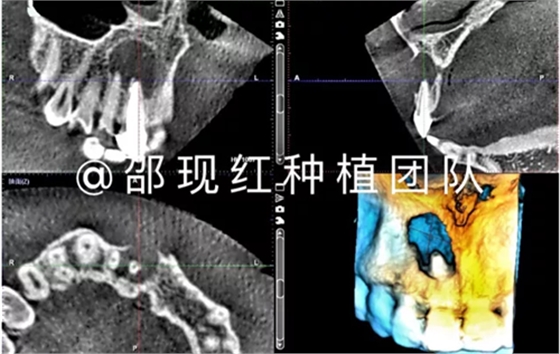

CASE ONE

11 12雙根尖聯(lián)合囊腫病例

「科普篇」你真的了解它嗎?——β-磷酸三鈣

術(shù)中使用科盧森骨粉